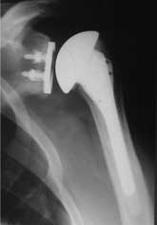

Sauf contre-indication (rupture de la coiffe, grande érosion osseuse de la glène), une prothèse totale sera posée. Cette dernière, modulaire, permet de reproduire d’une façon la plus exacte possible l’anatomie de votre épaule.

Dans la majorité des cas il s’agit d’une prothèse totale, c’est à dire qui remplace l’ensemble des surfaces articulaires de l’humérus, de la glène. L’utilisation d’une tige huméral ou d’un ancrage court dépend de l’atteinte osseuse. L’ancrage court permet l’utilisation des procédures mini-invasives.

Plus rarement Il s’agit d’une prothèse de resurfaçage humérale, c’est-à-dire qui remplace la surface articulaire de l’humérus uniquement. Cette cupule peut être mise en place par une technique de mini-incision.